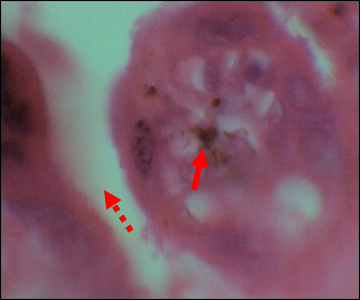

Overall (HIV+ and HIV-), 27.99% (82/293) of placentas showed no trace of malaria infection (Cat N). Category 1 lesions (Cat 1) were found in 19.45% (57/293) of placentas. Those of category 2 (Cat 2) were found in 29.01% (85/293) and lesions of category 3 (Cat 3) concerned 23.55% (69/293) of placentas. The lesions most frequently found in HIV+ mothers were those of Cat 2, 71/145, or 49.00% compared to 14/148, or 9.50% for HIV- mothers (OR=26.92; CI at 95%=11.10-67.60; p<0.0001). While Cat 3 lesions were more prevalent in HIV- mothers 46/148 (31.10%) vs 23/145 (15.80%), found in HIV+ mothers (OR=2.65; CI to 95%=1.15-6.21; p=0.020; (Table 4, Figures 1, 2, 3).

Figure 1 Microscopic picture of a category N showing villi (solid arrow) and an intervillous space containing maternal RBCs (dotted arrow). HE: x 40